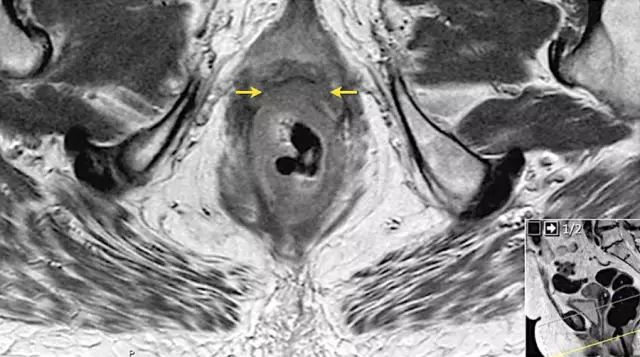

图 16 在矢状 T2W 图像上,直肠和阴道后壁之间有脂肪平面的损失。在轴向图像上,看到肿瘤的相对低的信号强度延伸到阴道的后壁(箭头)

图 17~21 肿瘤的低信号强度延伸到阴道的后壁(箭头)